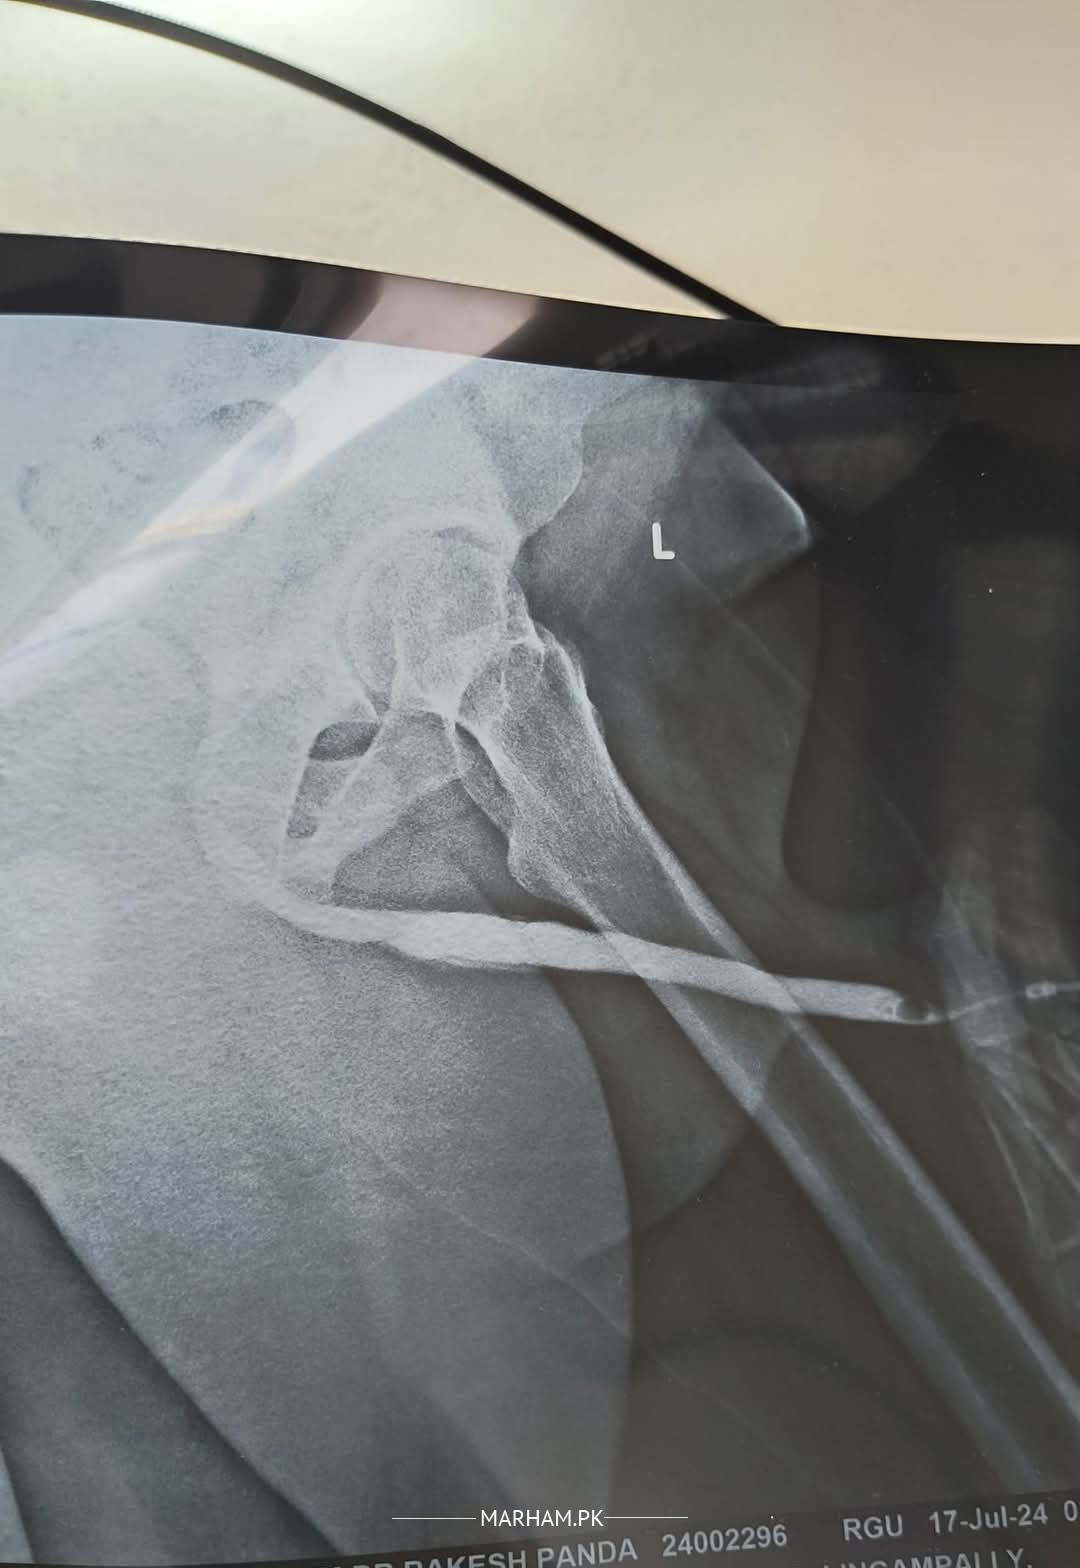

check RGU is normal or not

The film is not clear. Better to get reporting done by a radiologist before consulting a urologist.

this show any narrow ness

Picture quality is not good enough to comment. Also need more views for a proper comment. You should get a proper report for proper treatment.